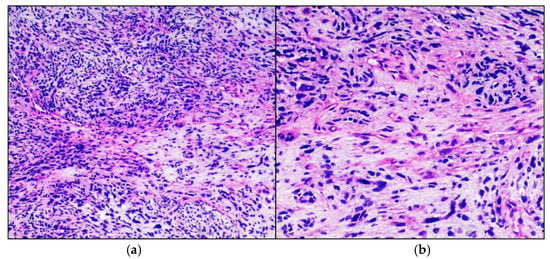

Intraoperative frozen section on stereotactic biopsy confirmed a high-grade glial lesion, in agreement with final histological and immunohistochemical diagnosis of high-grade midline glioma (Figure 3). Immunohistochemical investigations tested positive diffusely for acid gliofibrillar protein (GFAP) and focally for p53 protein; reactions for B-RAF, desmin and IDH-1 were negative. The H3.3K27M protein was not expressed. Fusion-transcript of NTRK1 gene was absent, while it was present for NTRK2 gene.

Figure 3.

High-grade glioma. Hematoxylin-eosin-stained photomicrographs with original magnification 100× (a) and 200× (b) showing diffusely infiltrating cigar shaped neoplastic astrocytes with obvious nuclear atypia.